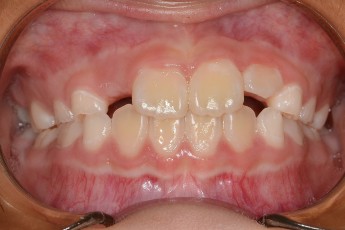

Before

After